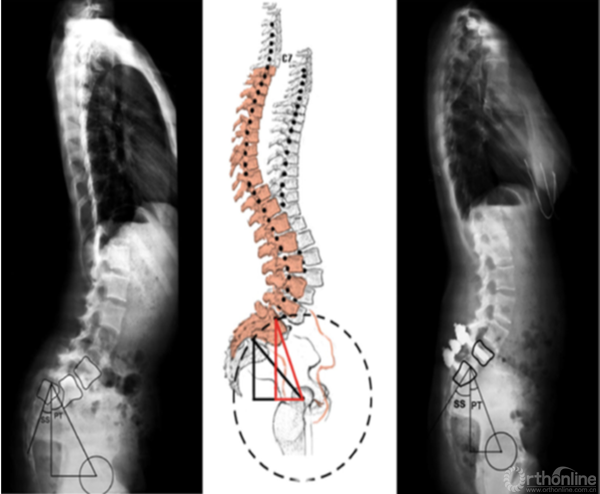

2. 骶骨形态不规则

骶骨形态不规则,通常是由于力学因素造成的。2012年,Sevrain[7]根据PI值将滑脱分为低PI组和高PI组,生物力学测试结果表明,低PI组人体重心位于骶骨中后区,而高PI组重心则分布在骶骨前方。从而更容易造成骶骨形态发生轻度或中度形态变化,L5椎体出现相应梯形变,从而亦会造成滑脱进展。

① 采取前后联合,骶骨部分截骨、复位和椎间支撑重建手术[8]。